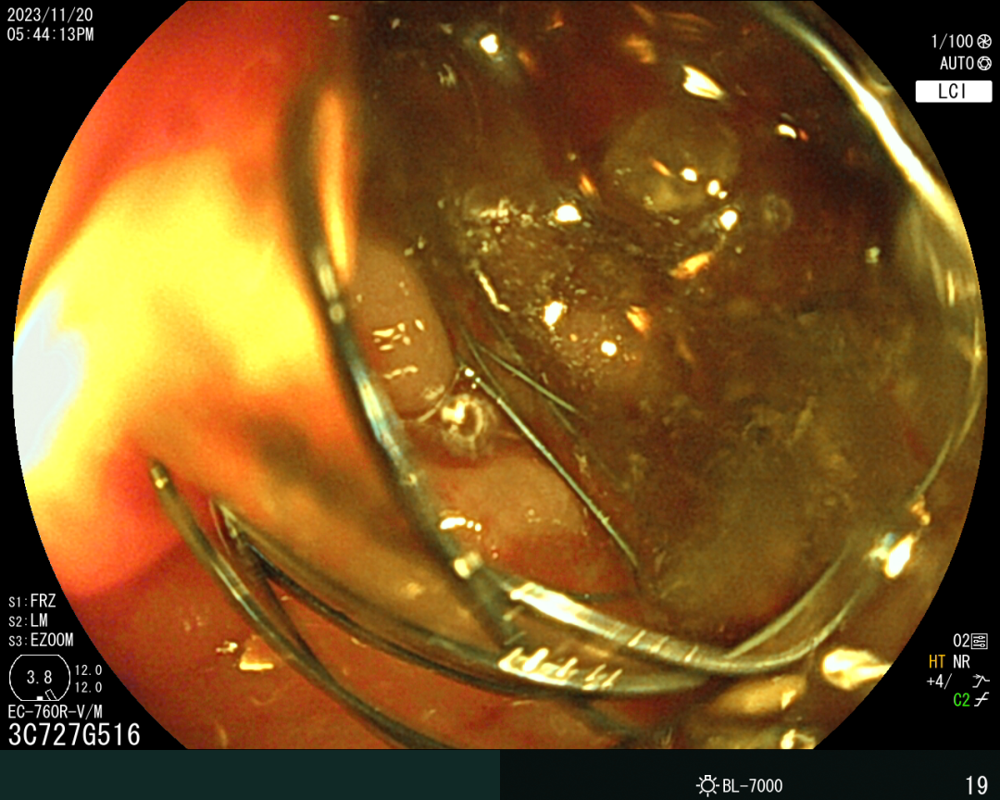

病例(lì)資料:患者,劉某某,男,73歲,因大便未解6天入院,伴有腹部脹痛(tòng),無嘔吐。入院查體;心(xīn)肺無異常、腹彭隆、壓(yā)痛、叩診呈鼓音(yīn),入院後急診腹部(bù)CT提示(shì)。乙狀結腸占位(wèi)並腸道梗阻(zǔ),急診腸鏡示:直乙交界新生物並腸道狹窄。患者於2023年11月(yuè)20日在介入室行腸鏡下腸道支架置入(rù)術,術中腸道流出糞水,術後第一天患者無腹痛(tòng)、腹脹,肛門恢複排便排氣,後複查CT示(shì)腸腔(qiāng)積(jī)氣積(jī)液明顯好轉,臨床療(liáo)效顯著。

(右)支架置入後